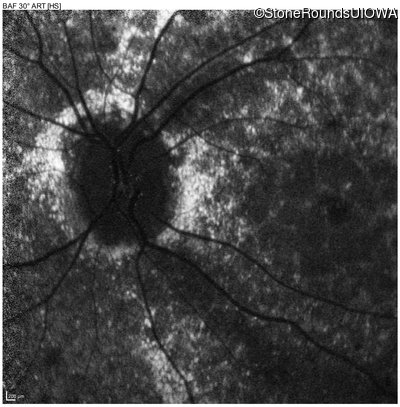

Blue Autofluorescence - Right - 10/700 sc

Exemplar

Blue Autofluorescence - Left - 10/400 sc